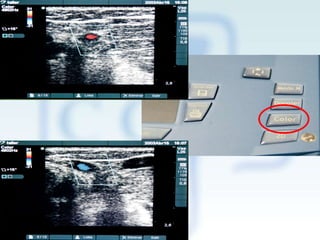

Ecografía doppler color

Muestra estructuras en movimiento en una gama de color

Mediante un código de color se muestra velocidad y dirección del flujo

Si el flujo se acerca: color rojo

Si el flujo se aleja: color azul

No detecta flujo cuando es perpendicular al haz de ultrasonido

Doppler color